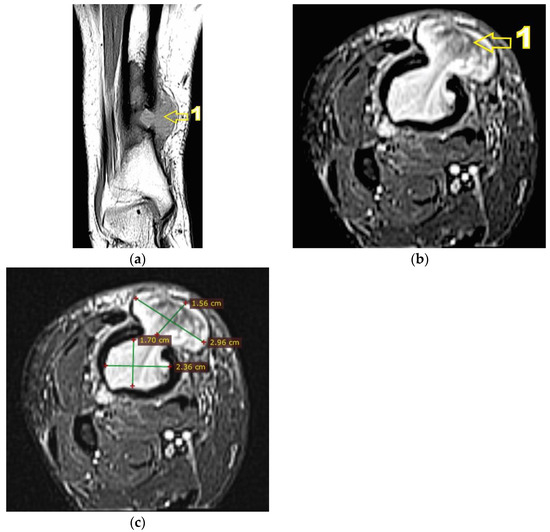

Corroborating the clinical examination with the patient’s history, we had decided to investigate again radiological and imaging (CT, MRI). Radiological and CT examination showed a slight increase in the size of the tumor formation, confirmed by MRI images (Figure 3), at this time the dimensions being 5.5/1.95/2.2 cm. Radiological and CT features were similar, osteolytic lesion with thinning and disruption of the bone cortex, associating periosteal reaction (Figure 4). However, this time, the CT images show the extraosseous expansion of the tumor formation, through the bone window created by the initial biopsy (Figure 5).

MRI examination clearly shows the extraosseous, subcutaneous expansion of the tumor formation through the cortical bone defect. This extraosseous expansion is in the continuity of the intraosseous tumor tissue, with the same imaging characteristics, having dimensions of 2.92/3.2/1.5 cm and well-defined edges, encapsulated (Figure 6).

Figure 4. (a) CT axial section. 1—disruption of the bone cortex; (b) CT axial section. 1—thinning of bone cortex, 2—periosteal reaction.

Figure 5. (a) CT axial section. 1—extraosseous expansion of the tumor formation; (b) CT coronal section. 1—extraosseous expansion of the tumor formation.

Figure 6. (a) MRI T1 hyposignal coronal section. 1—extraosseous expansion of the tumor formation; (b) MRI T2 Fat Sat (STIR) axial section. 1—extraosseous expansion of the tumor formation; (c) MRI T2 Fat Sat (STIR) axial section, tumor dimensions.